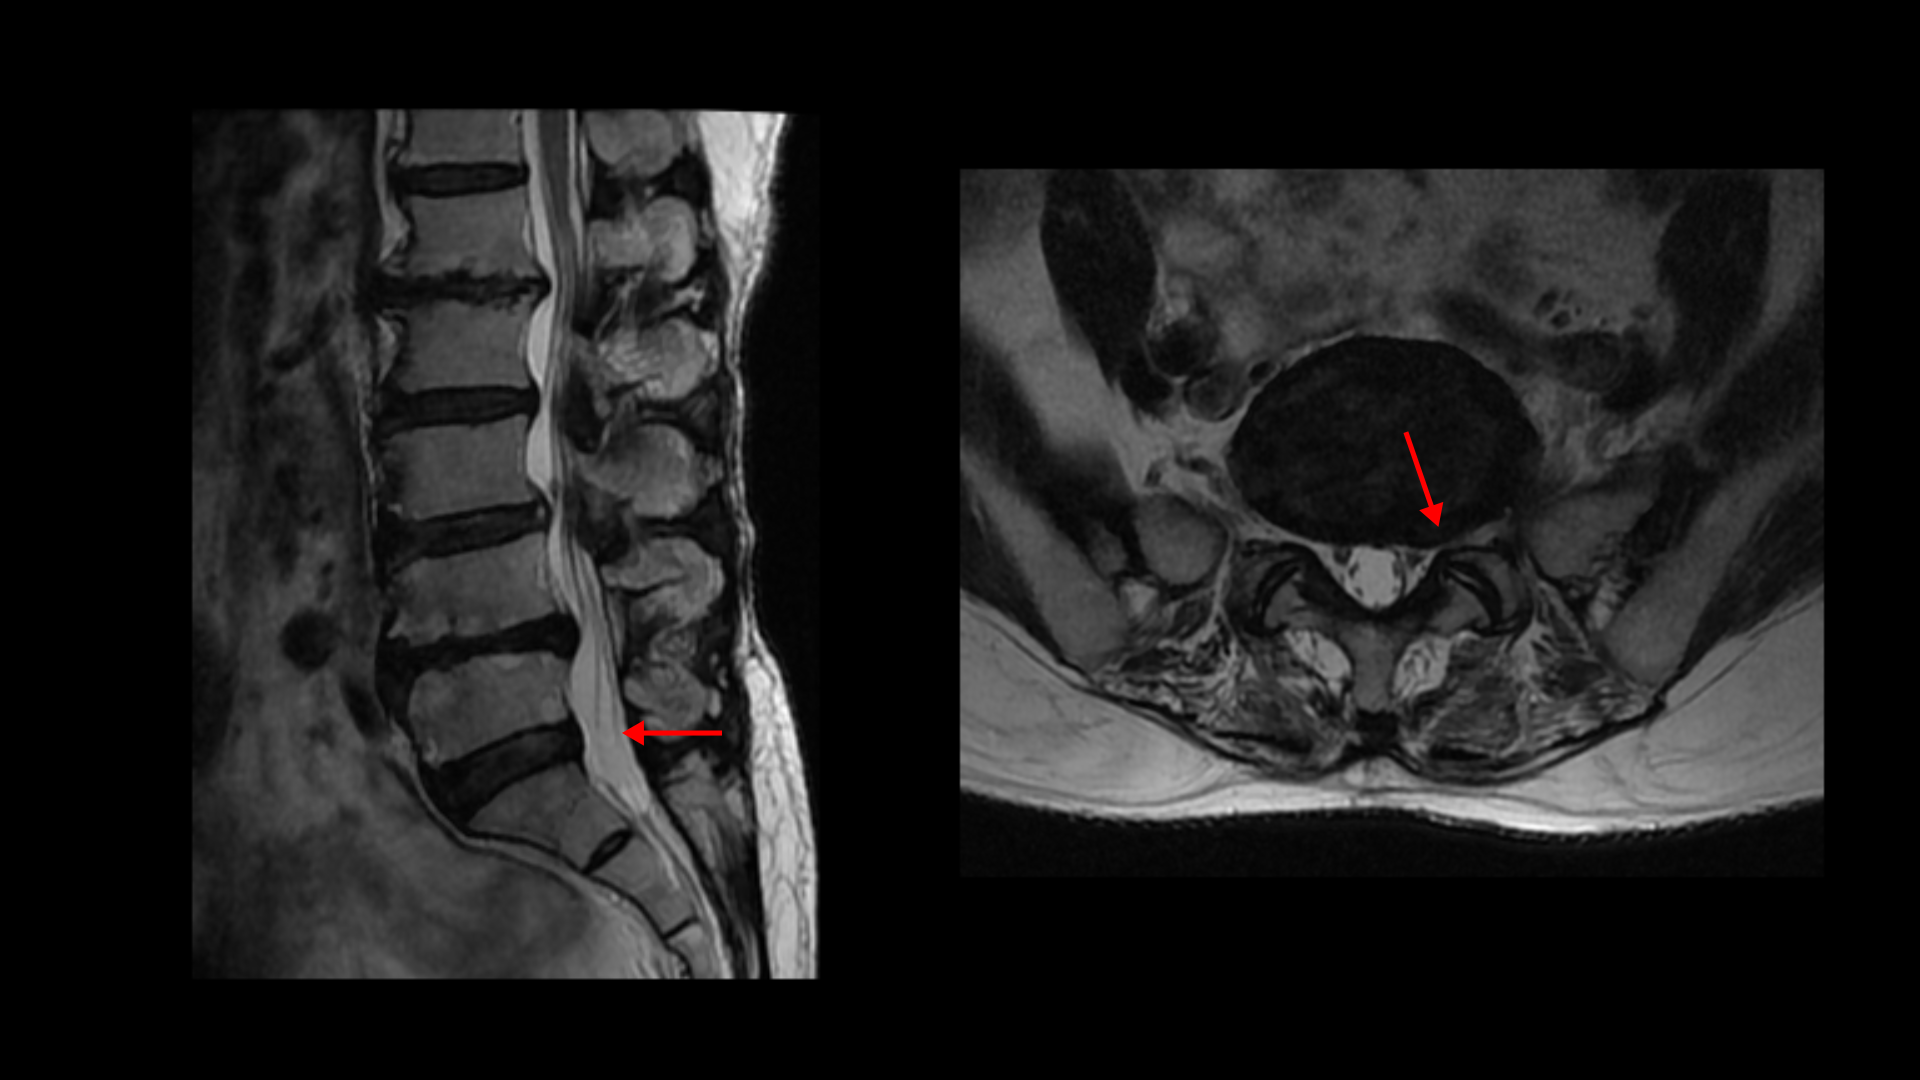

4-5번에는 왼쪽으로 디스크가 밀려 나와있고 심한 중심성 협착과 왼쪽 추간공협착도 있습니다.

5-1번에는 왼쪽으로 디스크가 밀려 나와있고 전반적으로 왼쪽이 상태가 더 안 좋은데 이분의 증상도 왼쪽 엉덩이와 다리의 통증과 저림 및 마비감입니다.